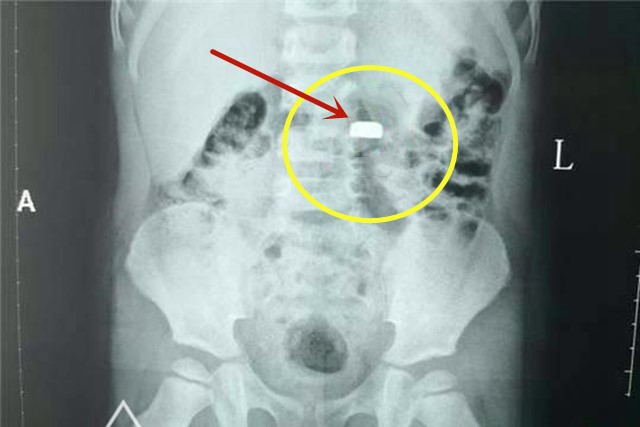

琳琳一家来到医院,跟医生说明情况,医生赶紧给安排做了CT。一检查,纽扣电池果真在孩子肚子里。医生给孩子做了手术,把纽扣电池取出来,孩子转危为安。